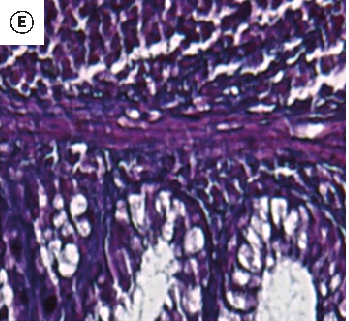

Figure 7

The Healing Effect of Aloe Vera Gel on Acetic Acid-Induced Ulcerative Colitis …